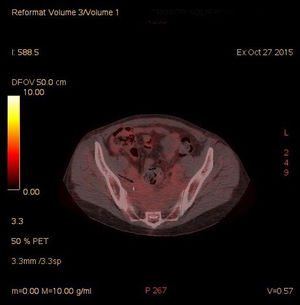

A thoracic-abdominal CT scan showed an extensive area of retroperitoneal (RPF) and pelvic fibrosis with bilateral ureterohydronephrosis. Subsequently a PET-CT scan with 18F-FDG (Fig. 1) confirmed the mass of soft tissues in front of the sacrococcygeal region, with low glucidic avidity (SUVmax: 2.16 g/ml).